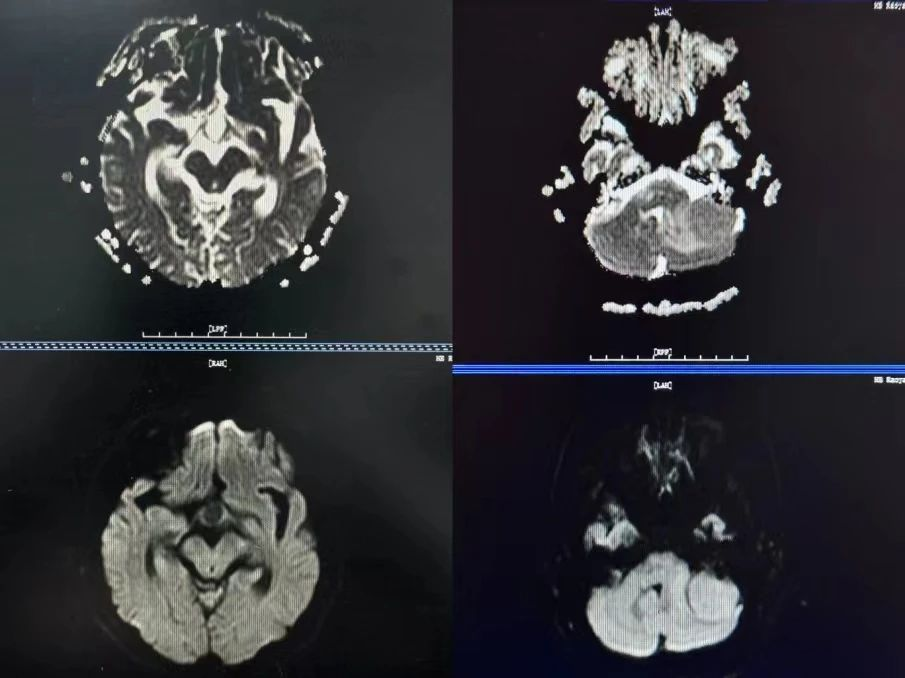

二是在脑外伤中的应用,DWI的优势是能够检查微小的脑挫裂伤。

三是鉴别良恶性病变方面。

四是对表皮样囊肿、脑脓肿等病变具有定性诊断的意义。

总之,DWI是磁共振临床应用中的一个非常重要的序列,当我们需要发现新发脑梗塞时,就进行DWI扫描;当我们检查脑外伤患者时,需要进行DWI扫描;当我们需要鉴别病变的良恶性时、对表皮样囊肿、脑脓肿等疾病定性诊断时,我们要进行DWI 扫描。